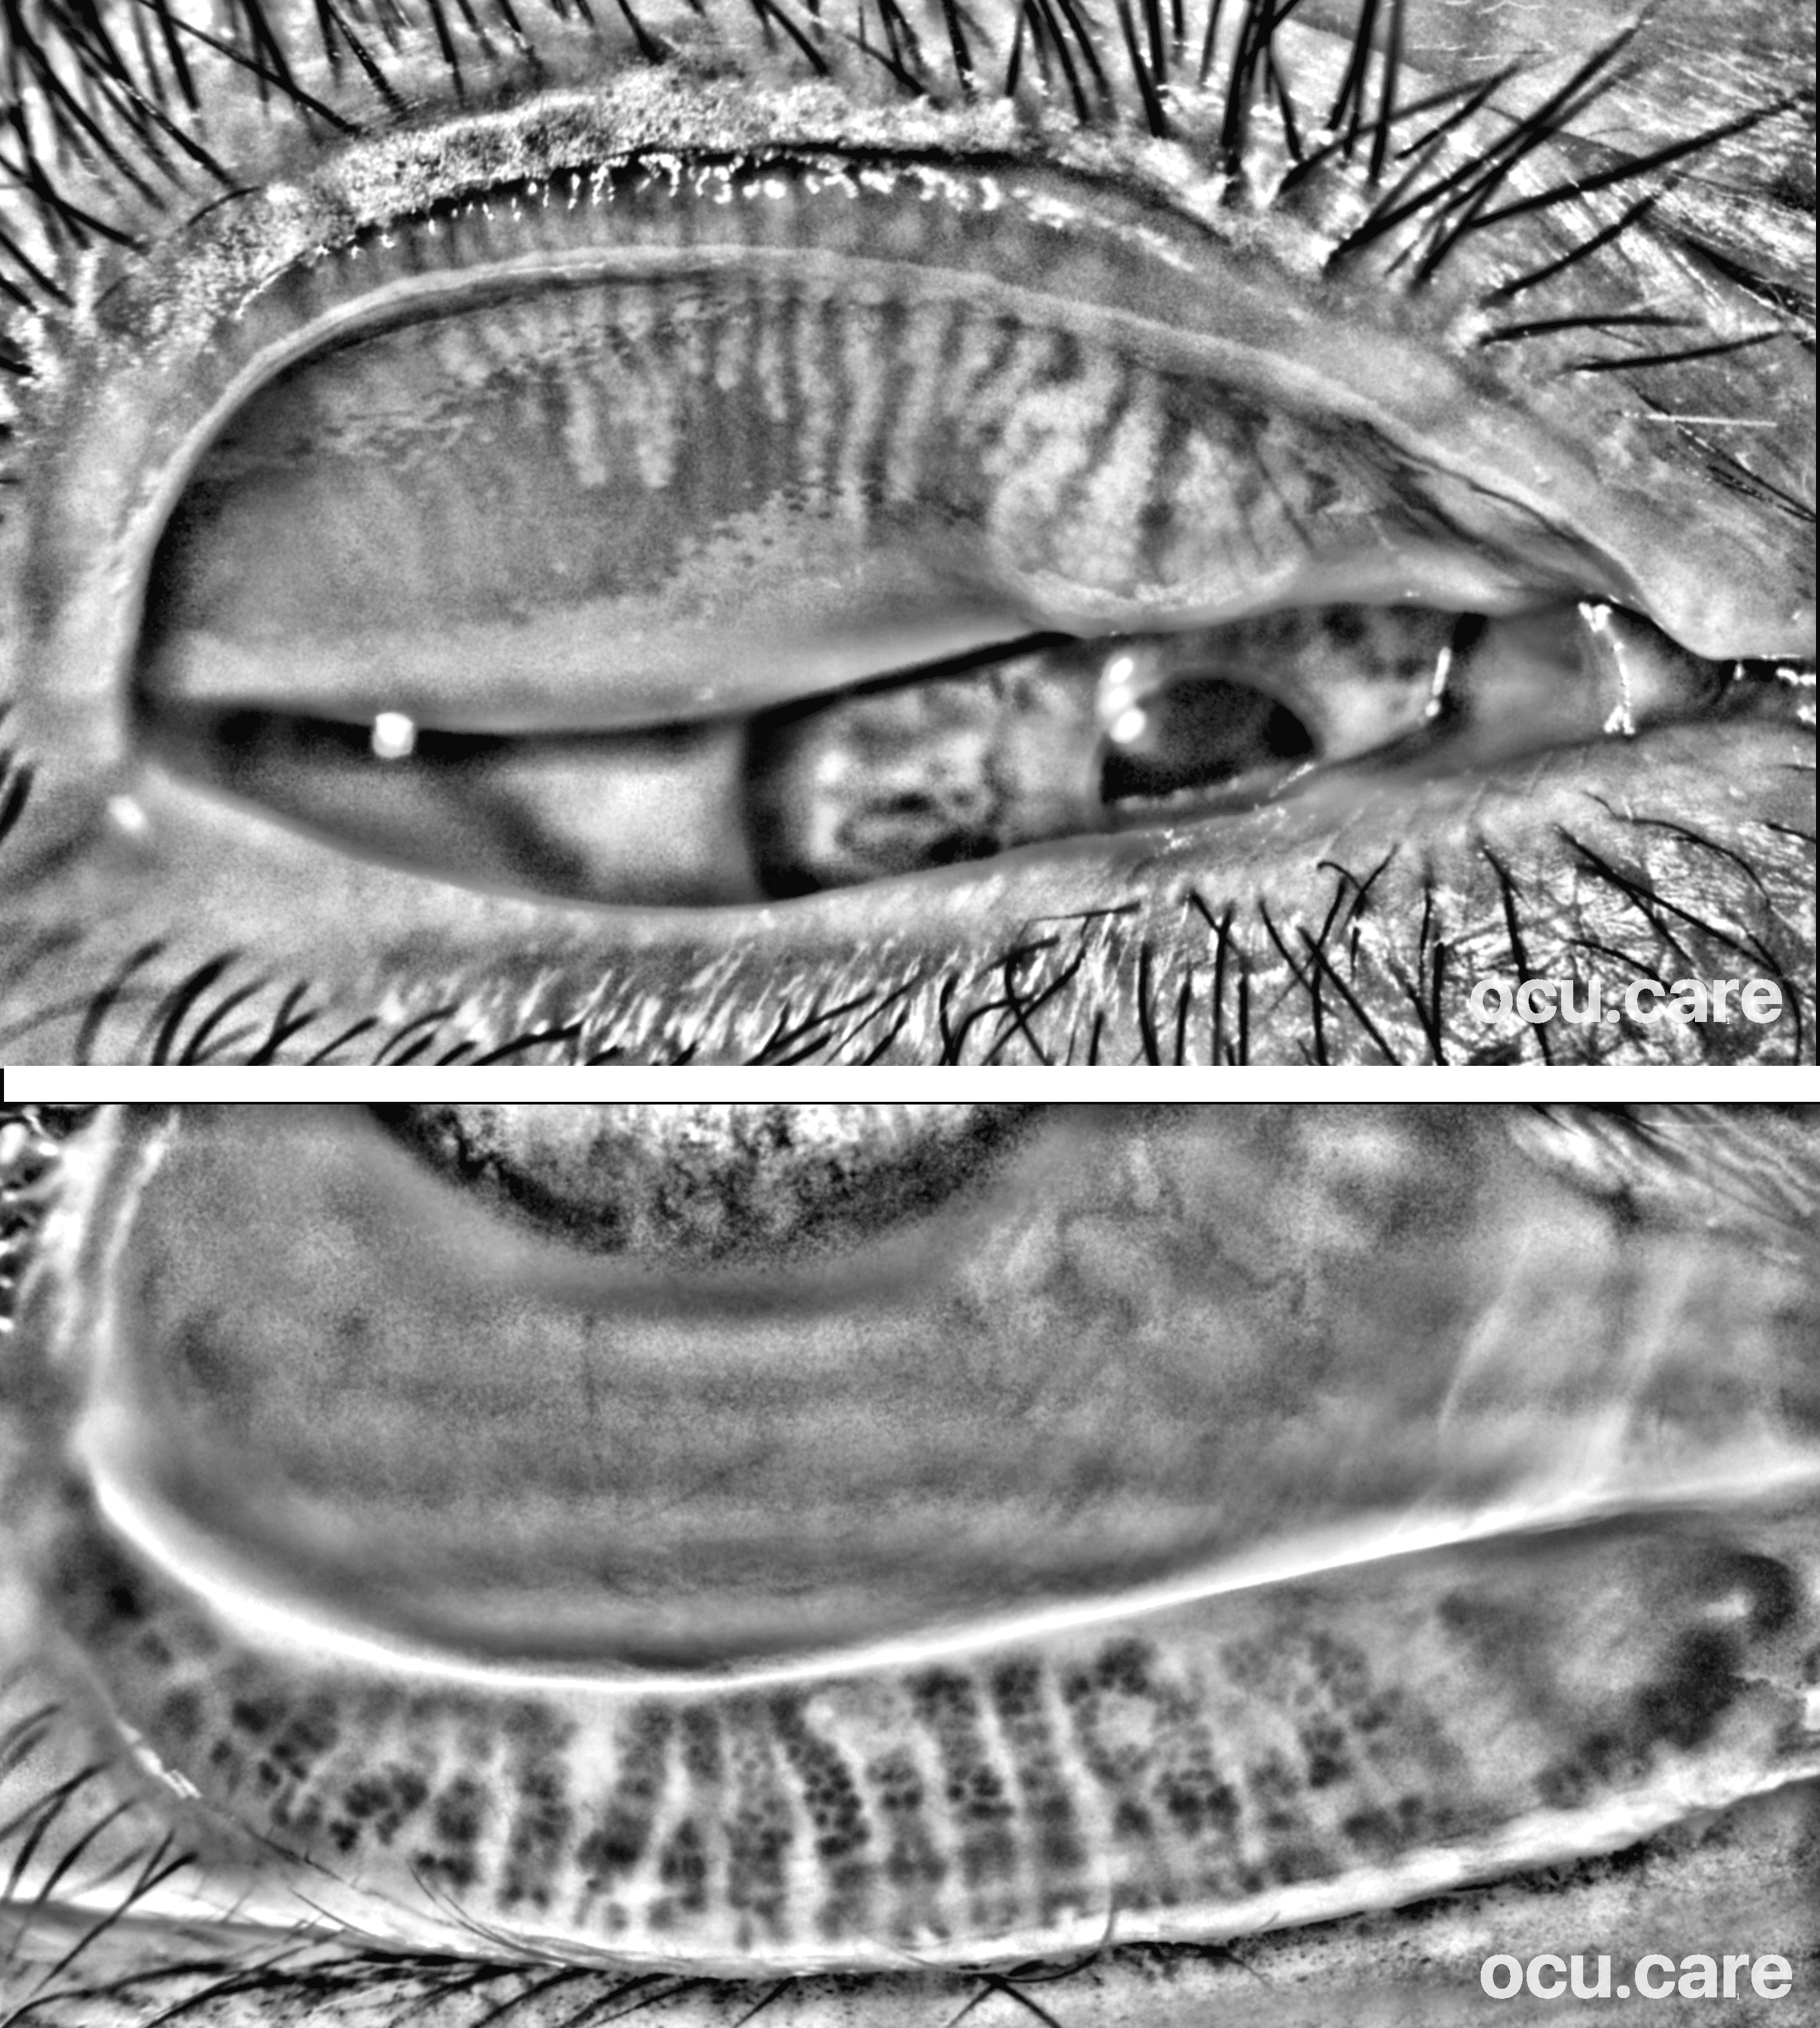

Lower lid meibography can look reassuring — but it may only be telling half the story

In this 66-year-old patient, the lower eyelid shows relatively preserved Meibomian gland architecture. The upper eyelid reveals marked gland dropout. Recent research suggests that preoperative upper eyelid gland loss may be a more relevant predictor of postoperative dry eye after cataract surgery than lower lid findings alone. Incorporating both eyelids into routine assessment can: • identify patients at higher risk • improve counselling and expectation management • support earlier, targeted intervention • document pre-existing gland compromise And perhaps most importantly — it changes the conversation with the patient. Because in many cases, what appears to be new dry eye after surgery… was already there — just not fully assessed. With MEA (handheld or slit-lamp attachment, by ocu.care), imaging both upper and lower eyelids is now simple, fast, and effortless. Tell the full story to your patient with MEA.